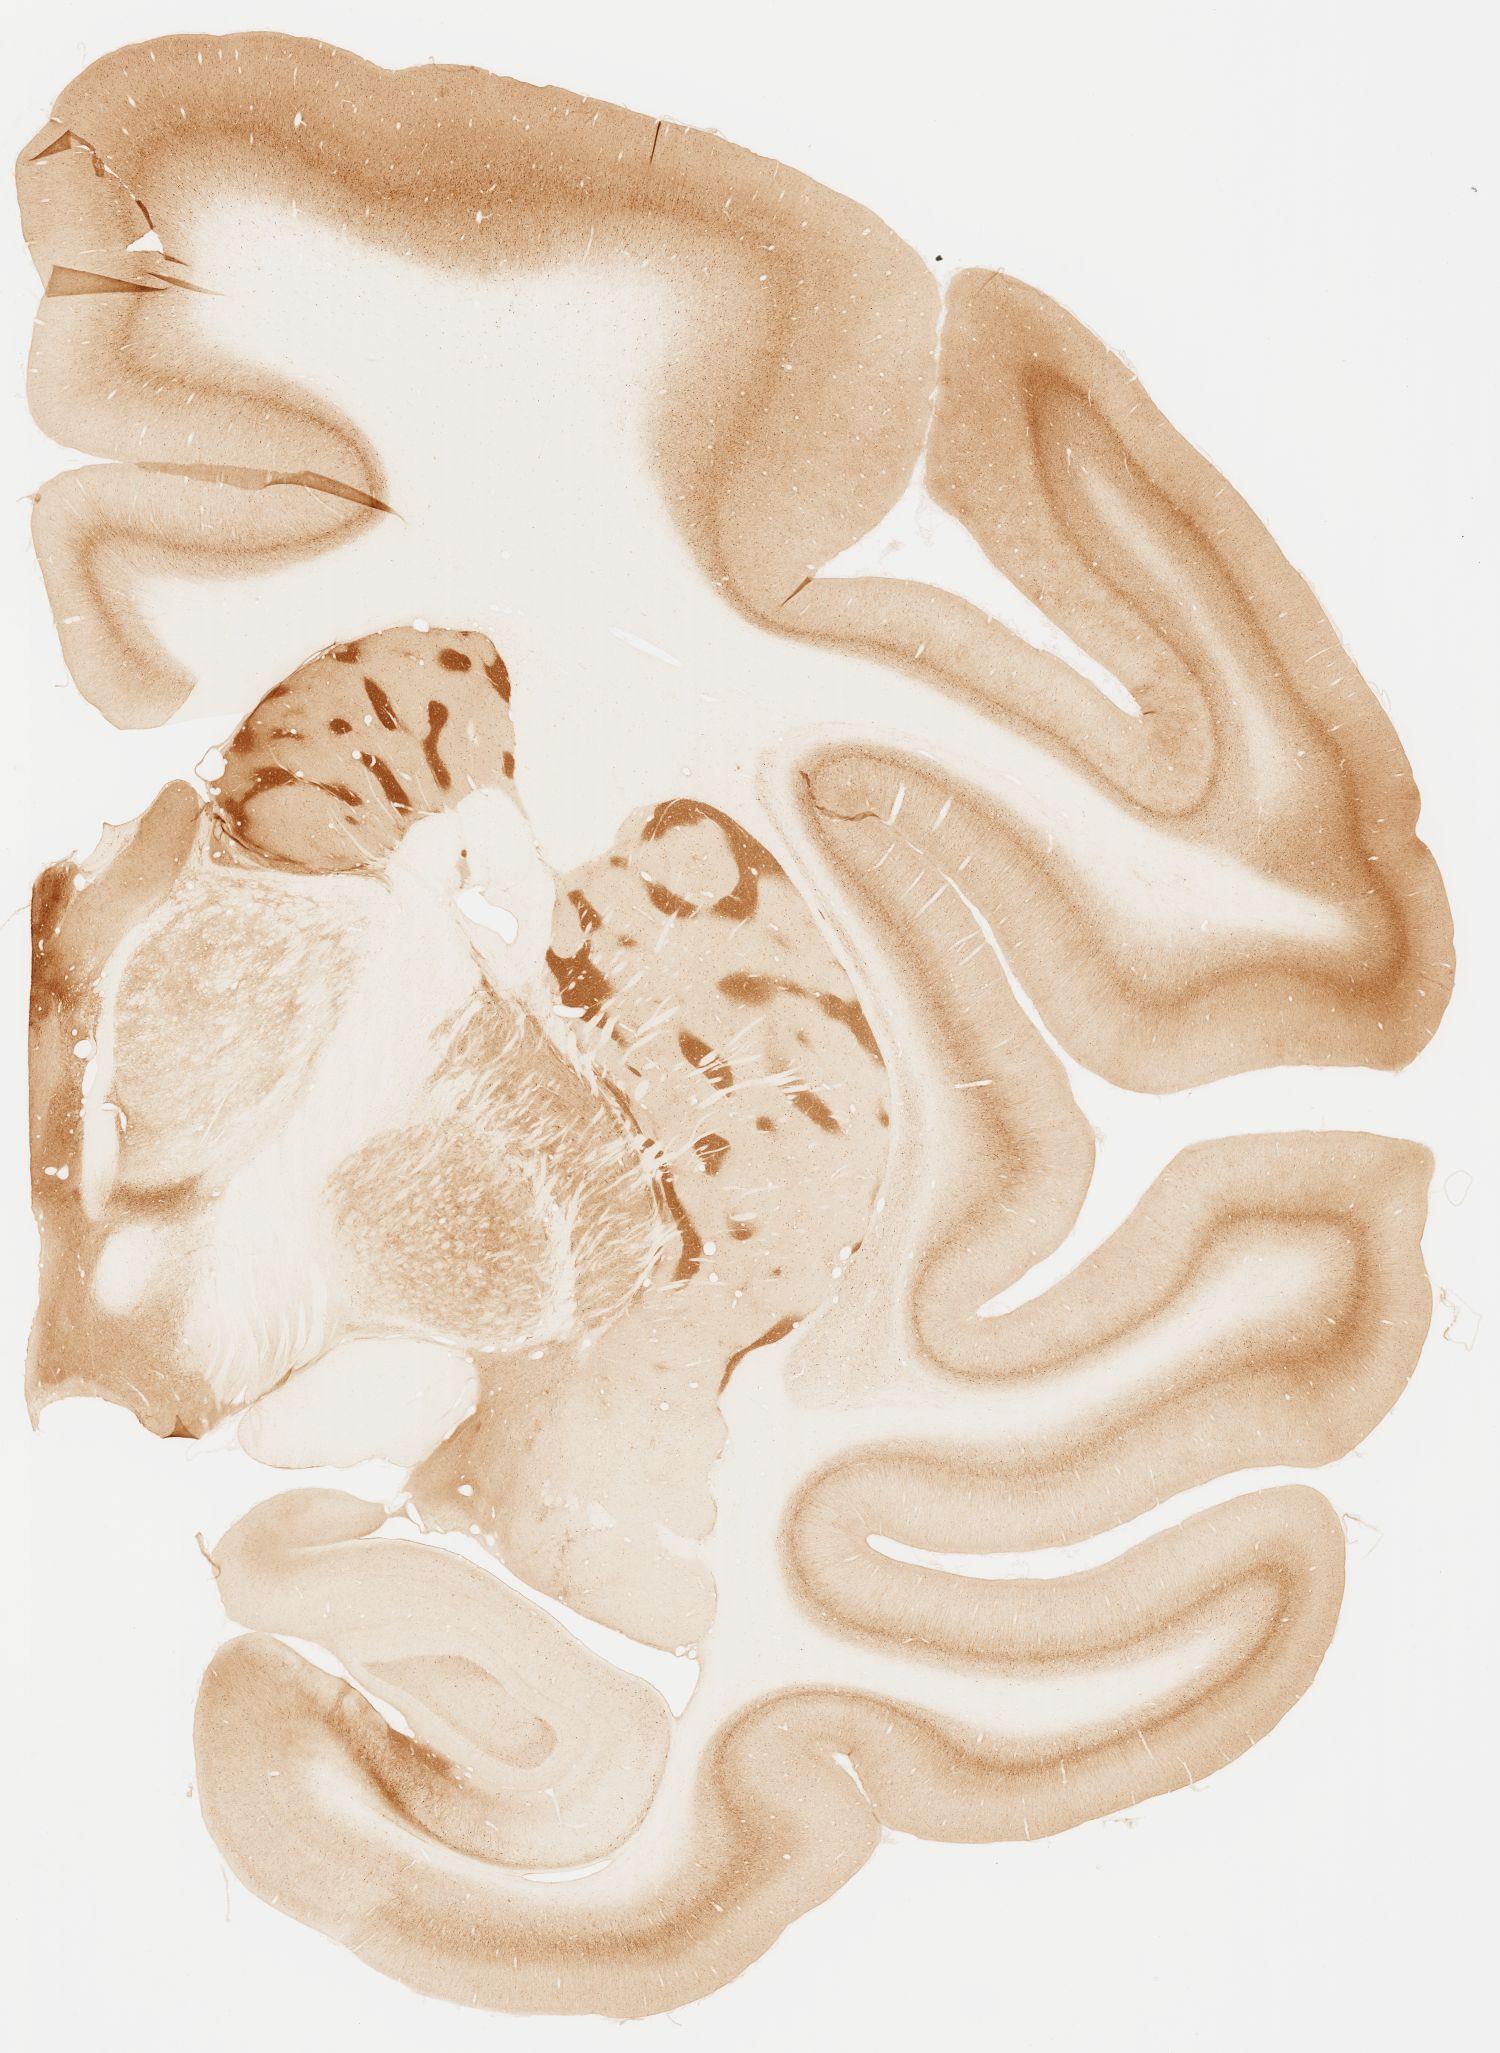

Datasets -> Macaca Fascicularis -> KChIP1, (Potassium Voltage-Gated Channel-Interacting Protein 1), coronal, immuno, Whole-Brain, adult

[ Metadata ]   ·   Source: Edward G. Jones

Displaying Sections 41 thru 80 of 92 Sections for this Dataset